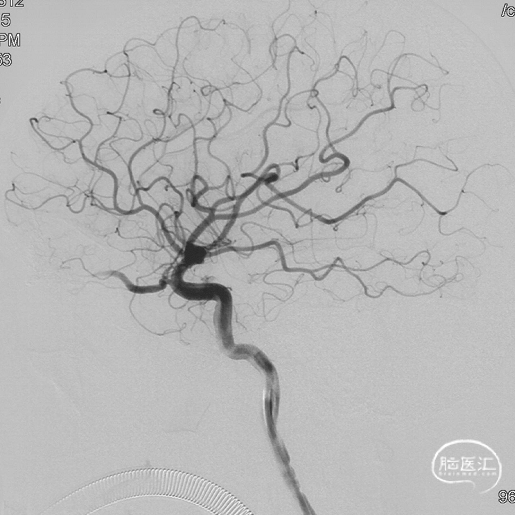

最终造影瘘口完全不显影。

双侧脉络膜染色正常。

Onyx胶铸型进一步显示了瘘的结构。AFA:镰前动脉;AEA:筛前动脉;PEA:筛后动脉;DV:引流静脉。

术后三个月造影复查,双侧颈内动脉、颈外动脉造影均未见静脉早显,DAVF治愈。